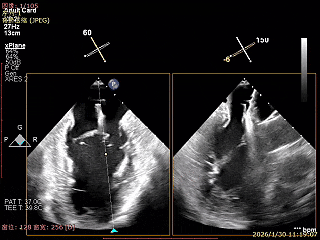

3D Enface下组织桥稳定无反流

夹子释放后,反流基本消失

LVOT切面可见主瓣二尖瓣术后反流基本消失

植入两枚夹子后二尖瓣平均跨瓣压差2mmHg